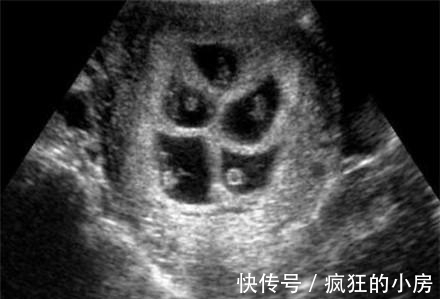

杨女士和丈夫结婚1年后发现自己怀孕了,全家人都高兴不已,特别是丈夫,因为他现在已经40岁了,要想他这样的年龄朋友的孩子都可以买酱油了。然而杨女士怀孕两个月的时候肚子大的出奇,实在放心不下,丈夫就带着杨女士到医院检查,检查发现原来检查结果出来了杨女士夫妻俩人是即高兴又担心,高兴的是医生说杨女士怀了四胞胎,担心的是杨女士的身体,这才两个月肚子就这么大了,要是再晚几个月可想而知。

医生说为了安全建议减胎,于是杨女士夫妻俩商量了一下,决定减胎。到了医院在做减胎手术前的检查时,医生的一句话又让她们犹豫了,说是五胞胎,要减三个,但是减三个的话手术危险挺大的,可能会导致胎儿流产,或终生不育,两人瞬间不知道怎么办了。